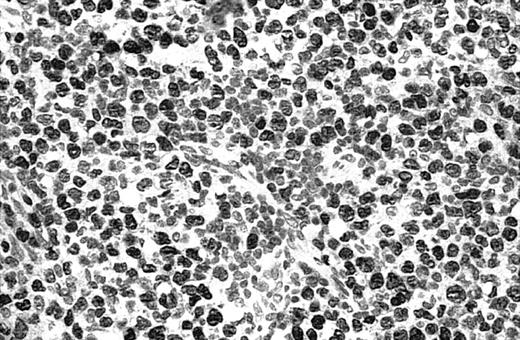

Of 69 PCLs analyzed by IHC, 44 cases showed nuclear JUNB expression in a proportion of tumor cells (64%) (Table 2). This included 21 (91%) of 23 SS, 6 (75%) of 8 C-ALCL, 5 (50%) of 10 MF, 9 (43%) of 21 PCBCL, 2 (50%) of 4 NK cell lymphoma, and 1 (50%) of 2 systemic FL (Table 2). Seven cases (10%) revealed expression of JUNB by all tumor cells (+++) (overexpression), including 5 C-ALCL (63%) and 2 SS cases (9%) (Table 2; Figures2-3). Epidermal basal and suprabasal keratinocytes also expressed JUNB, which represented a useful internal control to indicate the efficiency of immunohistochemistry (Figure 2). All the positively stained PCBCL cases showed only occasional cells expressing JUNB (+) (Table 2), and in this case it is difficult to conclusively establish whether expression is restricted to tumor cells or activated B cells on morphology.

Illustration of IHC staining of JUNB in an SS patient (case 8).

This photograph (original magnification × 40) revealed strong nuclear expression of JUNB by large epidermotropic tumor cells with absent expression in small dermal mononuclear cells. Epidermal basal keratinocytes also expressed JUNB, representing a useful internal control.

Illustration of IHC staining of JUNB in a C-ALCL patient (case 38).

This photograph (original magnification × 40) showed strong nuclear expression of JUNB by large anaplastic cells with no expression by small reactive lymphocytes.